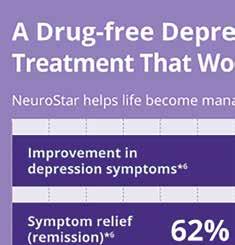

Are you a Veteran? Do you suffer from Depression, Anxiety, or OCD?

If anyone deserves to get your life back, it’s you. Let us help.

NOT medicine

NOT shock therapy

NOT invasive • IS safe and effective

• IS COVERED by most insurance

“I had taken 11 different medications without any relief… NeuroStar treatment has helped me bring my life back with a happiness that I’ve never experienced before” —TODD